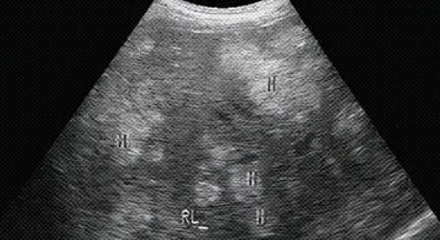

✔ B 型超声 (Brightness Mode)

最广为人知的「B 超 」,可以把回声信号转化为灰度图像。